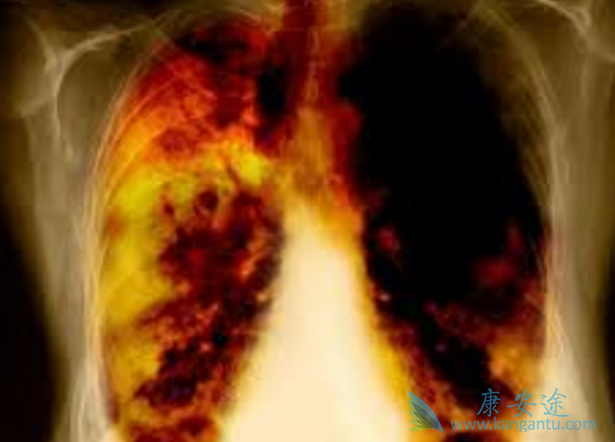

众所周知,药物副作用会影响患者对药物的安全性,就算是不致命的副作用但患者无法耐受也会是治疗中断。那服用肺癌药物吉非替尼(GEFITINIB)因副作用停药的几率大吗?吉非替尼最常见的药物不良反应为腹泻和皮肤反应,包括皮疹、痤疮、皮肤干燥和瘙痒,一般见于服药后的第一个月内,通常是可逆性的。大约8%的患者出现严重的药物不良反应。因不良反应停止治疗的患者有约3%。

各身体系统发生的不良事件按发生频率以降序排列(多见:]10%;常见:]1%且[10%;少见:]0.1%且[1%;罕见:]0.01%且[0.1%;极罕见:[0.01%)可出现的不良事件总结如下:基于在全球进行的临床研究,扩大用药/同情用药以及上市后使用中的数据,在日本以外的地区间质性肺病总的估计报告率约为0.3%,在日本约为3%。

一项双盲的III期临床研究中,比较吉非替尼(GEFITINIB)加最佳支持治疗(BSC)与安慰剂加BSC用于在既往接受过一个或两个化疗方案,且对最近的治疗无效或不耐受的局部晚期NSCLC患者,间质性肺病型事件的发生率在总体人群中相似,两治疗组均为约1%。绝大多数报道的间质性肺病型事件均来自东方人群,接受本品或安慰剂治疗的东方人群患者中,间质性肺病的发生率相似,分别为约3%和4%。一例间质性肺病型事件导致死亡,为接受安慰剂治疗的患者。